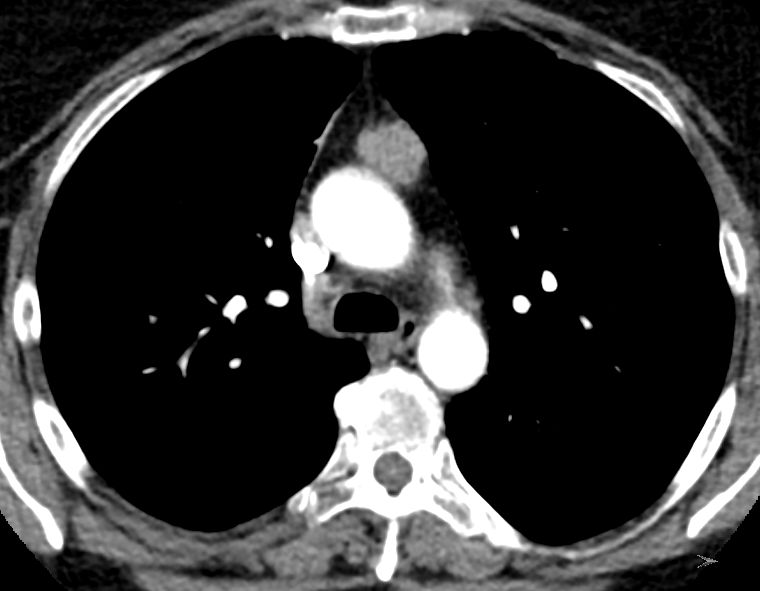

Diagnostik B3-Thymom mit Infiltration des Fettgewebes.